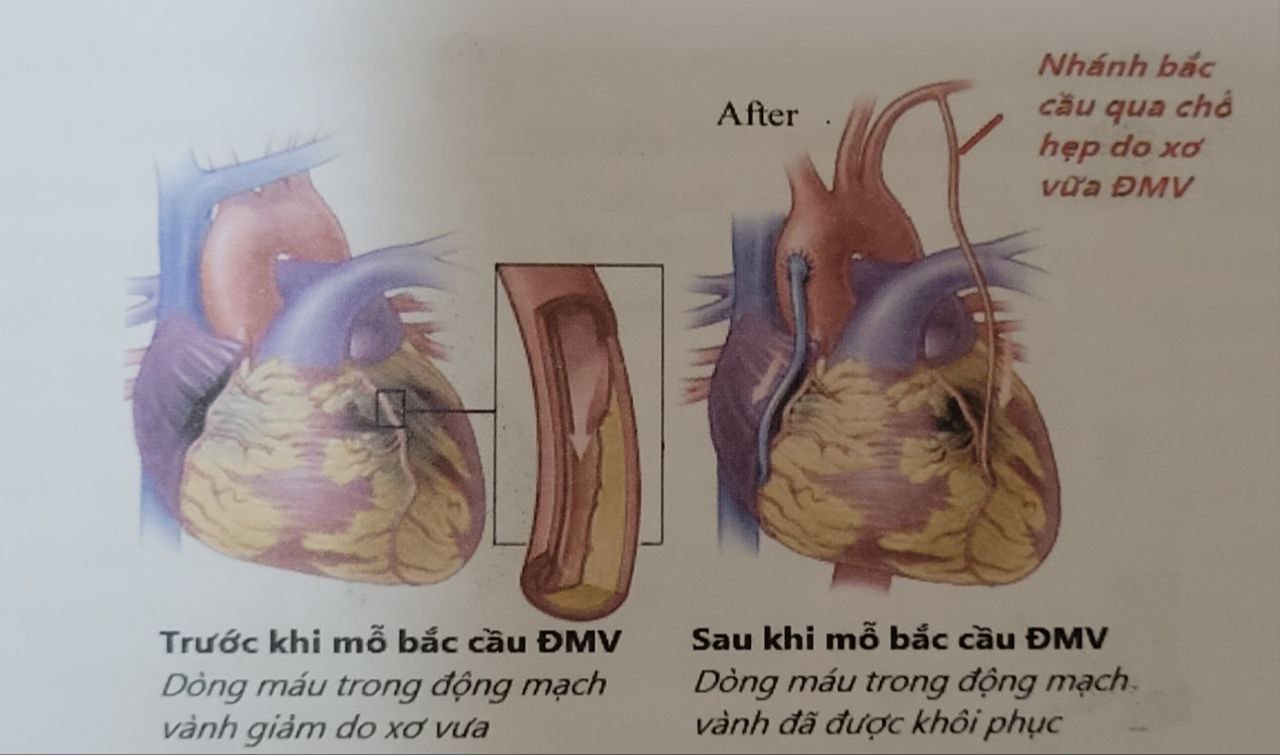

Động mạch vành (ĐMV) hẹp nặng và nhiều nhánh được mổ bắc cầu

Động mạch vành (ĐMV) hẹp nặng và nhiều nhánh được mổ bắc cầu

– Phẫu thuật bắc cầu động mạch vành: khi động mạch vành hẹp quá nặng nề (hẹp từ 3 nhánh động mạch vành hay nhiều hơn hay nhánh chính động mạch vành trái – thân chung động mạch vành trái) mà chức năng tâm thu tim giảm nặng hoặc hình thái động mạch vành quá phức tạp, vôi hóa nặng nề khó can thiệp thủ thuật động mạch vành qua da, lúc này phẫu thuật bắc cầu động mạch vành sẽ được chỉ định thực hiện, nhằm tái thông tưới máu động mạch vành.